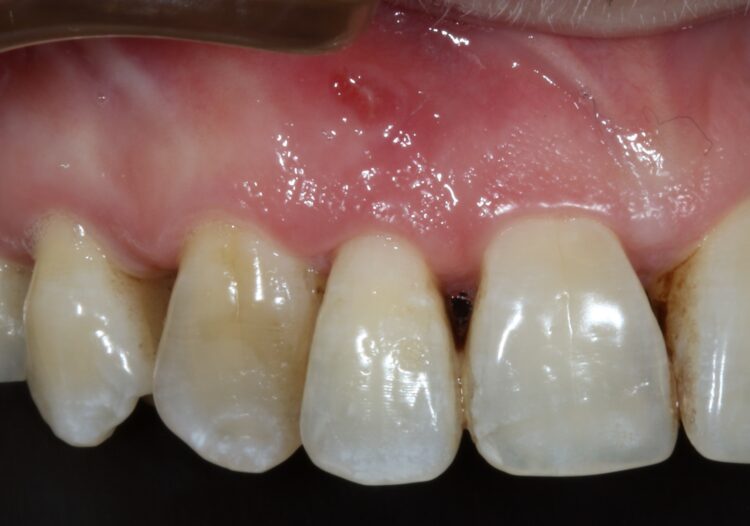

A female patient was referred for implant replacement of her failed upper right lateral incisor tooth. The tooth exhibited grade III mobility and had drifted forwards and downwards.

Clinical and CT scan assessment confirmed that the UR2 suffered from extensive bone loss with complete loss of the labial plate and was associated with a large periapical lesion which extended palatally and laterally towards the UR3. The UR3 tested positive to vitality testing.

Healing was uneventful and following a seven-month maturation period, a CBCT scan confirmed the presence of the MinerOss®/autogenous bone graft and a favourable volume of bone. However, it was noted that the soft tissues covering the bone graft were thin with an absence of interdental papillae. It was determined that a connective tissue graft would be required as part of the next surgical procedure to improve the soft tissue volume and lead to the creation of papillae during the prosthetic stages.